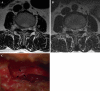

The objective of the study was to demonstrate the clinical characteristics of dural tears during percutaneous endoscopic lumbar discectomy (PELD) and to discuss how to prevent this unintended complication. The study used data from 816 consecutive patients who underwent PELD between 2003 and 2007. A total of nine patients (1.1%) experienced symptomatic dural tears. The clinical outcomes were evaluated using the visual analogue scale (VAS), the Oswestry disability index (ODI), and modified MacNab criteria. Intractable radicular pain was the most common symptom, while classical manifestations, such as CSF leakage or wound swelling, were rare. In three of the nine cases, the dural tears were detected intraoperatively, while the remaining six cases were not recognized during the procedure. Among the unrecognized patients, two patients were found with nerve root herniation causing profound neurological deficits. All patients were managed by secondary open repair surgeries. The mean follow-up period was 30.8 months. The mean VAS of radicular leg pain improved from 8.3 to 2.6, and that of back pain improved from 4.1 to 2.6. The mean ODI improved from 69.6 to 29.2%. The final outcomes were excellent in one, good in five, fair in one, and poor in two patients. As application of the endoscopic procedure has been broadened to more complex cases, the risk of dural tears may increase. Unrecognized dural tear with nerve root herniation may cause permanent neurological sequelae. Accurate information and proper technical considerations are essential to prevent this unpredictable complication.